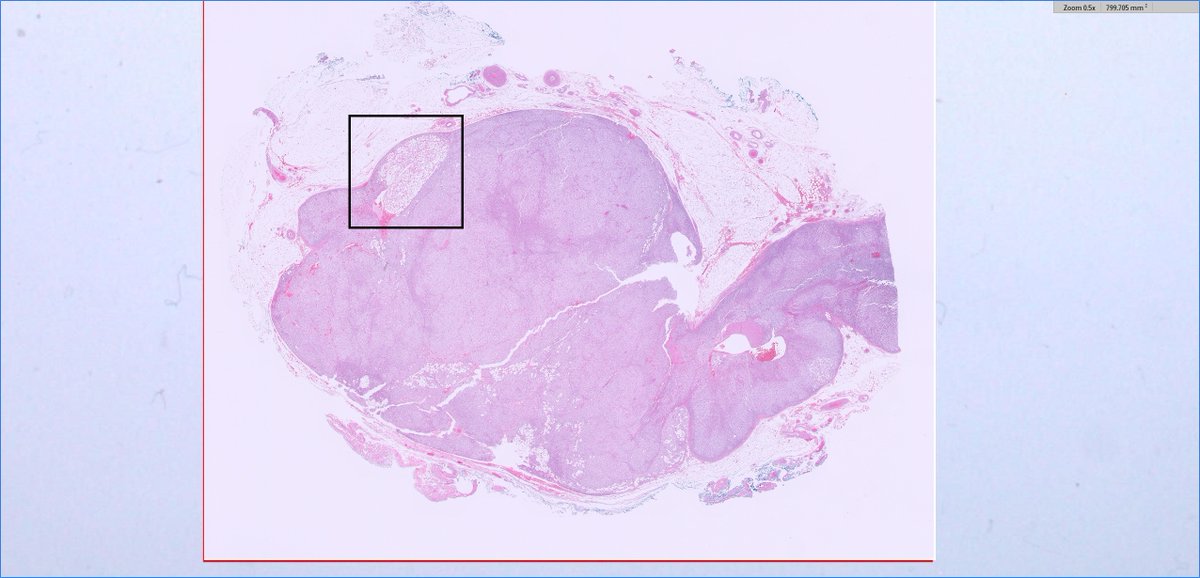

#endopath: adrenal myelolipoma

slusagar's tweet image. #endopath:

adrenal myelolipoma